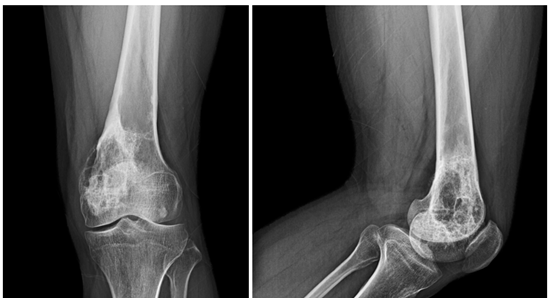

患者入院后摄片,左膝关节X线片示:左股骨远端见片状偏心性不均匀密度增高影,累及高度近10cm,局部骨皮质增厚、局部骨皮质变薄欠连续,病灶局部见硬化边。